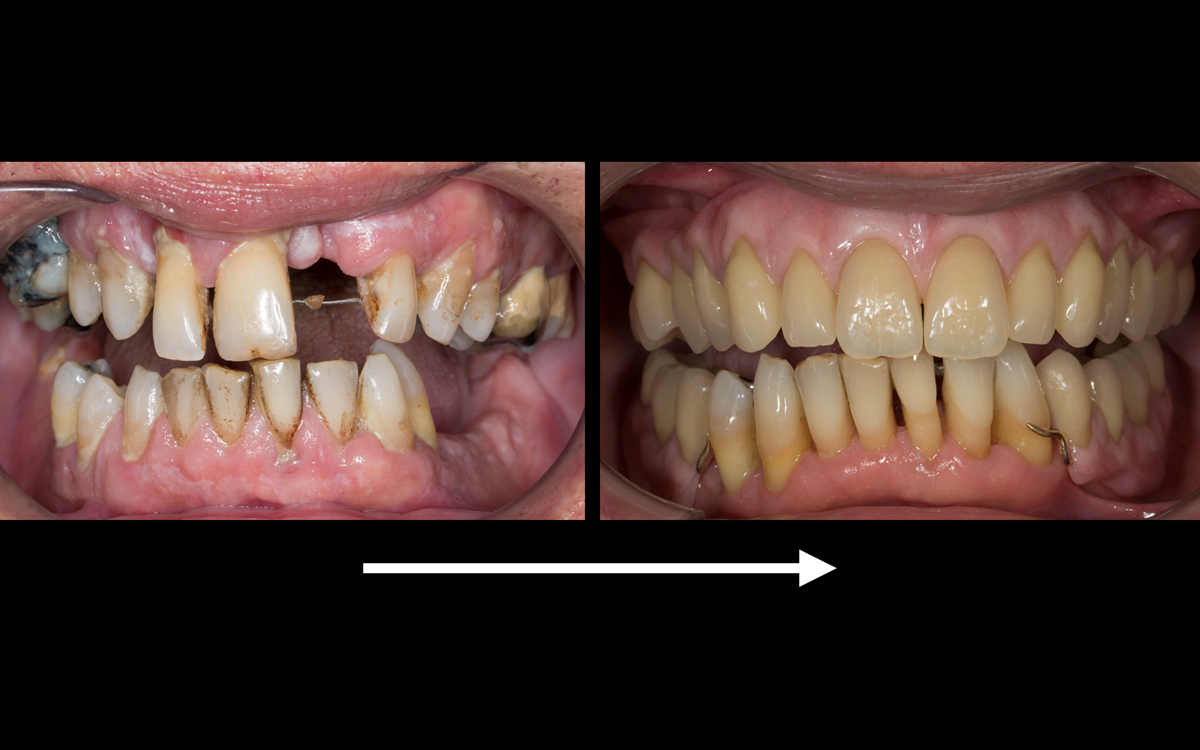

This newsletter describes in step by step detail the transition from acrylic based immediate dentures to metal based definitive dentures.

This 52 year old man was referred to me from his general dental practitioner in 2018.

10 years prior to consultation the patient's general dentist diagnosed periodontitis and referred him to Manchester Dental Hospital. He received a treatment plan to manage the periodontitis. Unfortunately, this was not acted on. Four years ago gaps developed between the upper front teeth. Orthodontic treatment was provided to align the teeth. A bonded retainer was fitted onto the upper front teeth. Approximately one year prior to consultation with me the patient noticed the teeth moving again. He consulted his orthodontist, who advised no further orthodontic treatment. One month prior to the consultation with me the upper left central incisor fell out whilst eating.

- Generalised periodontitis; stage IV grade C: currently unstable, risk factors: smoker.

- The remaining maxillary teeth had hopeless prognosis in the short term. They exhibited 80 - 100% alveolar bone loss with increased mobility (Grade 2 - 3).

The clinical situation and treatment process is shown in detail below with photographs.

The patient has been successfully rehabilitated and is now having periodontal maintenance from Syed Abad, Specialist in Periodontics at the practice. His quality of life has improved considerably. The clinical prosthodontics was provided by me and the technical work by Rowan.